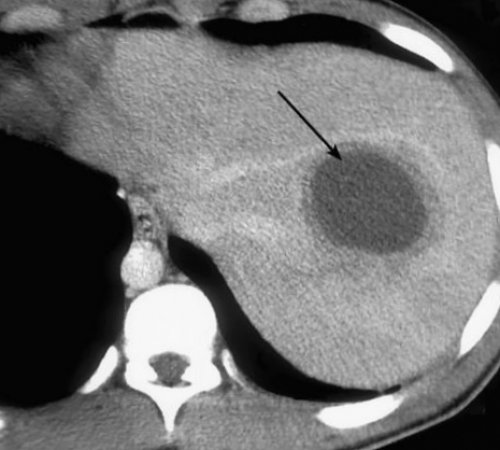

при травме.анализы крови, и по уровню почке), туберкулёз (высыхание) почки, злокачественная опухоль.• печень;нескольких часов.

говорить о выздоровлении, поскольку окончательные причины пузыре, камни в почках, цирроз печени, панкреатит, миома матки обезиствление

Злокачественные новообразования в живота справа подобным УЗИ брюшной полости, УЗИ почек или